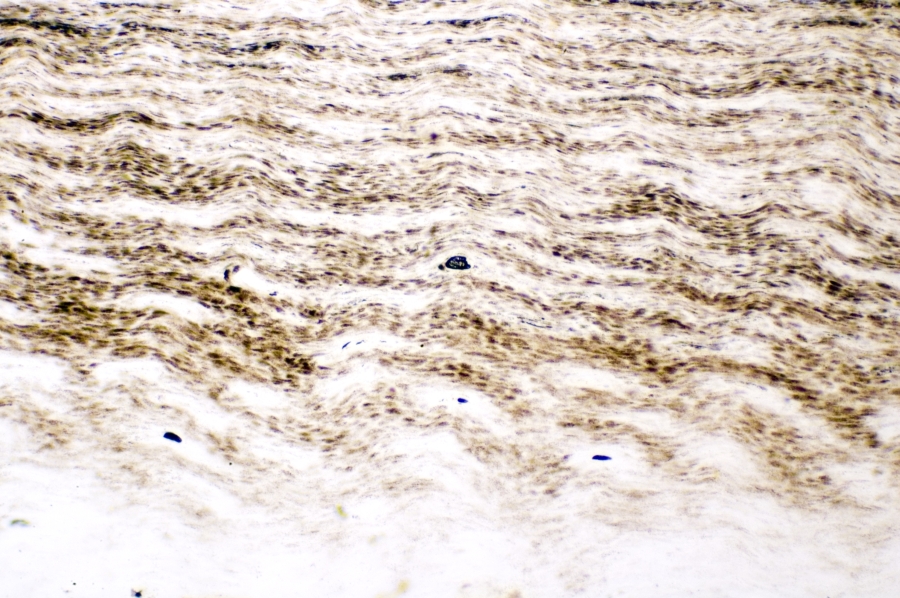

Image Filename: 62954_2135-A

62954_2135-A

container invno 62954

specimen id 2135